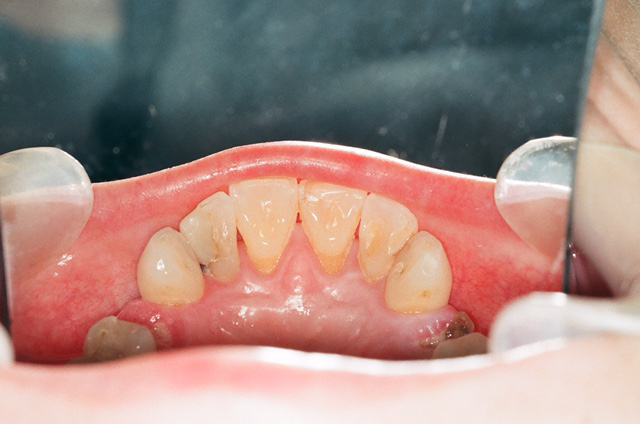

During the clinical exam, I identified that the patient’s pain was originating from the maxillary right first premolar. This tooth was fractured, had pulpal involvement and a periapical lesion, and was non-restorable (Fig. 2). The patient had generalized decay, gingival recession and attrition throughout her mouth. Although the caries was not blackened, the decay pattern (Class V anterior lesions and coronal fractures) was consistent with methamphetamine abuse (Fig. 3).

Fig. 2 Fig. 3